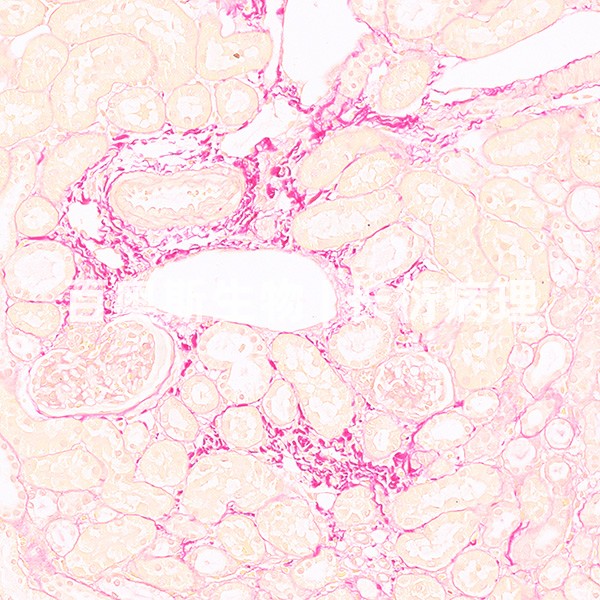

- 探索PAS染色的艺术:关键技巧与安全实践